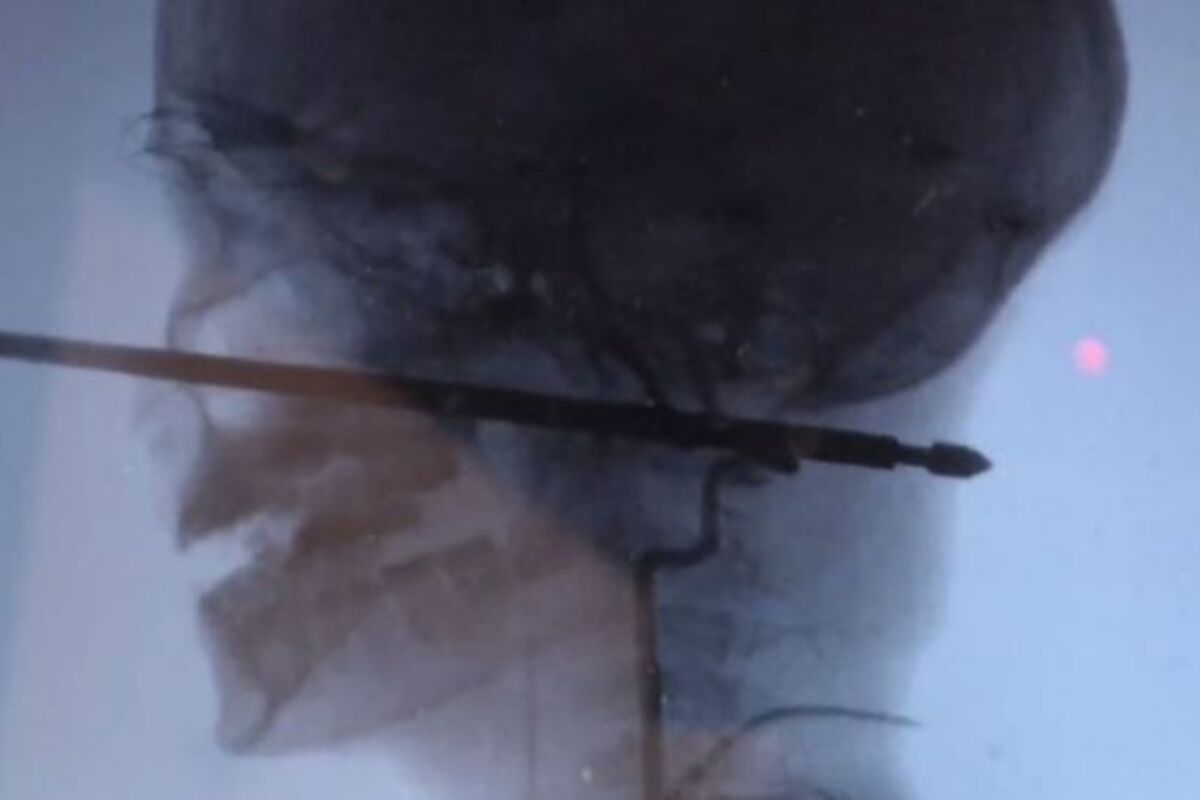

NAPALE SU GA OSICE, PA JE PAO GLAVOM PRAVO NA RAŽANJ! Dečak (10) je uspeo da preživi neverovatnu povredu! (VIDEO)